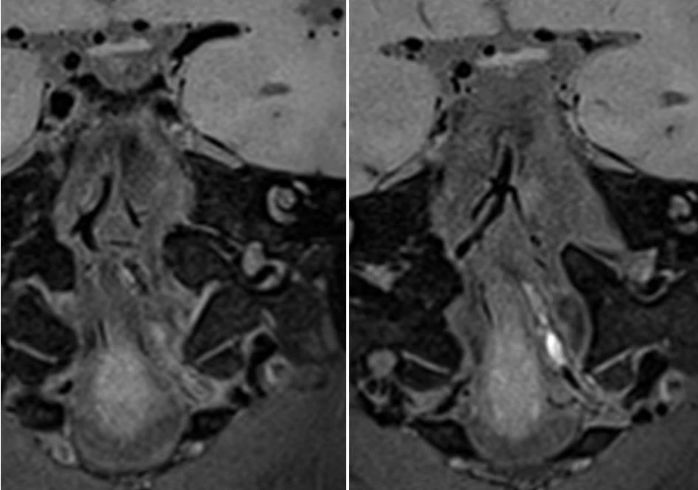

高分辨磁共振:左椎动脉闭塞,管腔可见高信号血栓,负荷量较大。右椎动脉管壁增厚,管腔狭窄(图7)。